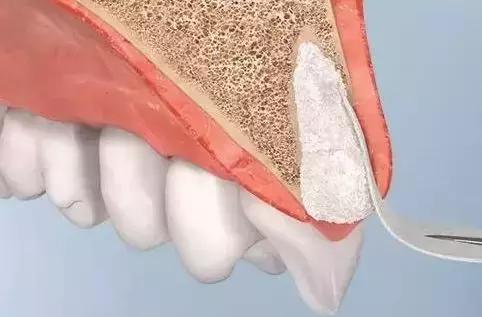

Sclar 于 2004 年首次提出较为规范的拔牙位点保存技术,即在拔牙窝内植入异种骨粉颗粒,表面覆盖可吸收性胶原膜以修复牙槽骨缺损。

GBR(guided bone regeneration引导骨再生技术):将生物膜固定在软组织和骨缺损之间,利用生物膜屏障阻止生长速度更快的上皮细胞和成纤维细胞长入,创造出骨组织优势生长的环境,成骨细胞优先进入骨缺损,无竞争生长。通常还配合骨缺损处的骨移植。

说人话就是:骨头缺损的地方呢就好比空着的“地盘”,牙龈、根周膜和牙槽骨都想占上,但是呢,软组织的细胞跑得快呀,骨组织的细胞跑得慢呀,怎么样能让骨组织给占上呢,招标。用招标的方式——生物膜把软组织隔开,把“地盘”圈起来,让骨细胞慢慢跑,都是骨细胞的。

那么,骨粉起啥作用呢?把骨细胞比作行进缓慢的步兵的话,骨粉好比工兵搭建的桥梁,可以帮助骨细胞跨越较大的缺口,直至抵达胜利的对岸。

生物膜除了能促进骨组织优势形成,还能防止植入物泄漏,协助创口封闭。

在牙槽嵴扩增术的众多技术中,GBR 是目前公认安全、有效、可靠的骨增量技术。